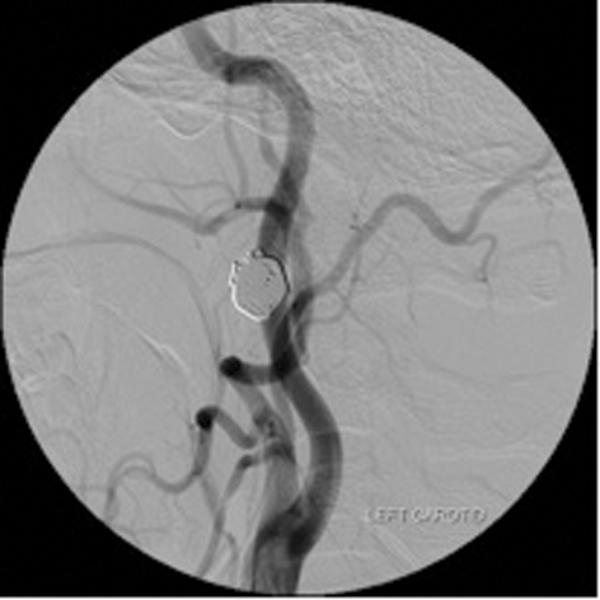

Embolisation is also effective in paragangliomas (glomus tympanicum, glomus jugulare and carotid body tumours). These are tumours arising from paraganglionic chemoreceptor cells which receive their blood supply from the ascending pharyngeal artery. They can be multicentric, locally invasive with malignant potential. Preoperative embolisation of paragangliomas greatly facilitates surgery and reduces the operative time and reduces the associated morbidity [3, 4]. (Figure 2 shows a case of preoperative embolisation of a glomus vagale tumour).

Figure 2: Glomus vagale before and after embolisation.